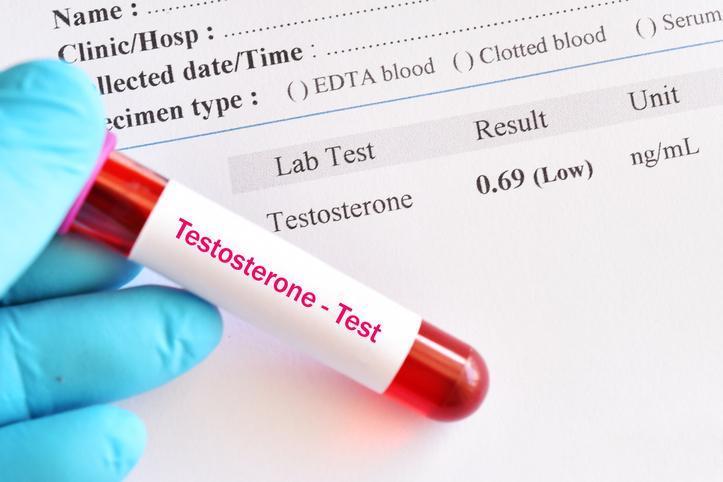

4) TESTOSTERON SEVİYELERİNİ NORMALE ÇEKMEK

Shah, "Hormonlarımın dibe vurduğuna dair en ufak bir fikrim yoktu. Ancak testosteron seviyelerimi ölçtürdüğümde 42 yaşındaki bir erkek için çok düşük olduklarını gördüm" dedi.

Cleveland Clinic kaynaklarına göre, düşük testosteron cinsel isteksizlik, iktidarsızlık, keyifsizlik ve vücutta yağlanma gibi sorunlara yol açabiliyor. Shah, hormon replasman tedavisi aldığını ve testosteron seviyelerini normal kabul edilen aralığa yükselttiğini söyledi.

20/22

Shah'ın hormon seviyeleri üzerinde yaptığı yaşam tarzı değişiklikleri de etkili oldu. Cleveland Clinic kaynaklarına göre, sağlıklı beslenmek, egzersiz yapmak, sağlıklı bir kiloda kalmak, aşırı alkol ve madde kullanımından kaçınmak, testosteron seviyelerini normal tutmaya yardımcı oluyor.

Öte yandan bir zamanlar tabu kabul edilen testosteron replasman terapileri son dönemde resmi olarak "düşük testosteron" teşhisi almamış erkekler arasındaki popülerliğini artırıyor.

Erkekler testosteron alımının kas kütlesini artırmaya, daha güçlü ereksiyonlara ve daha enerjik olmaya faydalı olduğunu belirtiyor. Ancak bu terapilerin genç ve sağlıklı erkekler için faydalı olup olmadığı net değil. Dahası testosteron alımı akne, saç dökülmesi ve kısırlık gibi yan etkileri de beraberinde getirebiliyor.